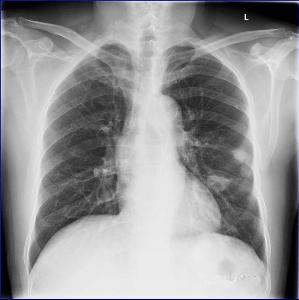

肺隐球菌病为新型隐球菌感染引起的亚急性或慢性内脏真菌病。此菌属腐生酵母菌,不形成菌丝和孢子,广泛存在于自然界中。机体免疫功能低下为发病的主要诱因。